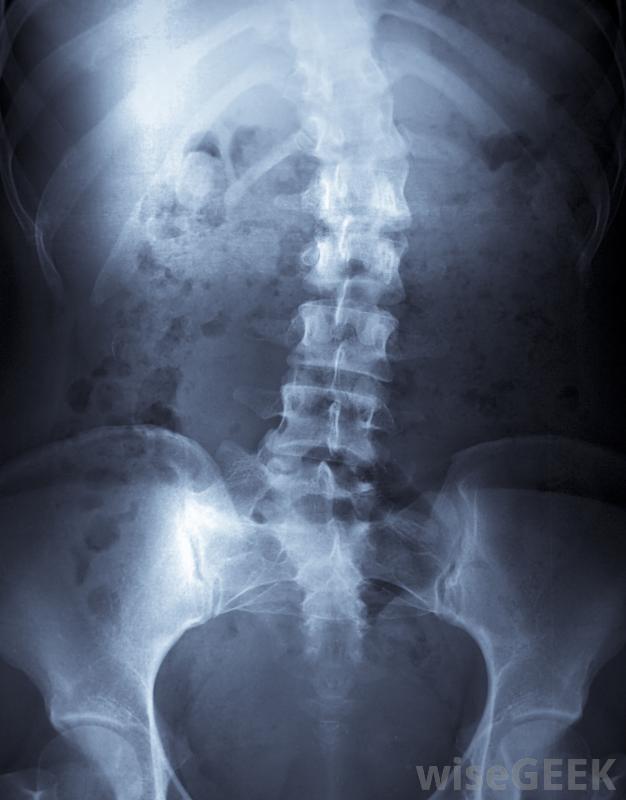

矯形器是一種幫助人們更好或更安全地移動的裝置,或者在身體某個部位必須受到限制時防止移動。矯形師可以制作各種矯形器支架,它們通常是根據患者的具體問題和獨特的體型定制的。可以為背部定制一個支架,以幫助減少疼痛例如脊柱側凸時脊柱的彎曲。其他矯形器支架可用于治療影響腳、腿、脊柱、手臂或手的各種問題。矯形器支架可用于治療脊柱側凸,即脊柱的異常彎曲。矯形器支架可以用來幫助支撐脆弱的關節,如腳踝、膝蓋或肘部。這些裝置也可以幫助矯正或改善運動,包括人的步態,或者它們可以防止受傷或減輕疼痛。有些矯正器,如某些脊柱側凸矯正器,為了達到預期的效果,每天只需佩戴特定的時間。其他類型的矯正器在需要矯正時都會佩戴,例如為了使病人能夠行走而佩戴的矯形器支具,醫生也可以通過改變身體的排列方式來減輕神經的擠壓和相關的疼痛踝足矯形器支架可幫助某些患者恢復活動能力為了制作矯形器支架,矯形師首先必須制作一個能戴上矯形器的身體部位的模具。模具的制作非常像為斷肢制作的石膏,實際上它類似于一個石膏。矯形師然后用這個模具用熱塑性材料制作一個支架。在某些情況下,矯形器支架需要多個配件,以達到適當和舒適的配合,不會因在某些區域過度摩擦而傷害皮膚,例如踝關節的骨性部分。一種被稱為踝關節矯形器(ankle and foot orthosis)的矯形器常被用于脊柱裂、腦癱、跌跤、肢體畸形、中風、多發性硬化癥的患者,脊髓灰質炎或截癱。這些患者還可以使用KAFO(膝、踝和腳矯形器),可以達到大腿的高度來幫助支撐膝蓋,除了腳踝和腳。頸托是一種類似的保護頸部的裝置。